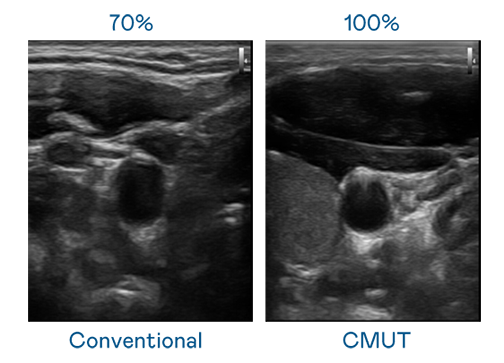

CMUT 技术是一种用电容式微机电元件来产生超音波讯号的技术。与传统 PZT 压电式技术相比,CMUT 频宽增加 30%,更宽频的超音波讯号让影像解析度大幅提升,是实现高影像品质医疗超音波扫描、促进精准医疗发展的关键技术。

大频宽带来超清晰影像

超音波影像的解析度高低,首先取决于探头能发出的讯号频宽。太阳集团城娱8722 CMUT 可提供高清晰的超音波讯号,提供高频宽、高灵敏度、影像纹理细节更高的超音波影像,协助医护人员缩短影像判读时间及利用精准的医疗影像进行诊断。